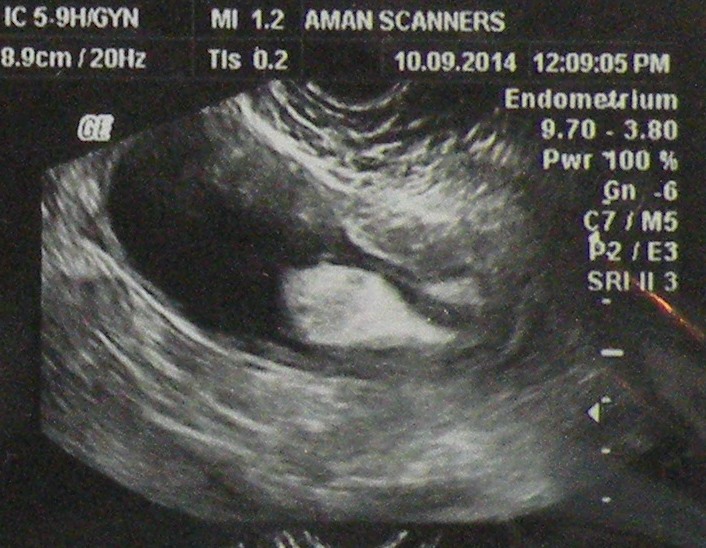

20.11.14 An adult intussusception, diagnosed on US and CT, in a 50-years old female, presenting with sub-acute intestinal obstruction of many weeks, was treated by resection of the segment of distal ileum bearing the intussusception. On cut section, it was found to contain a big pedunculated benign-looking tumour arising from the ileum.